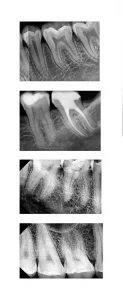

RVG technology in Dentistry has revolutionized the way dentists approach radiography, offering numerous benefits:Enhanced Image Quality

RVG provides high-resolution images, critical for accurate diagnosis and treatment planning. The clarity and detail offered surpass traditional X-ray films, allowing for better detection of dental conditions.